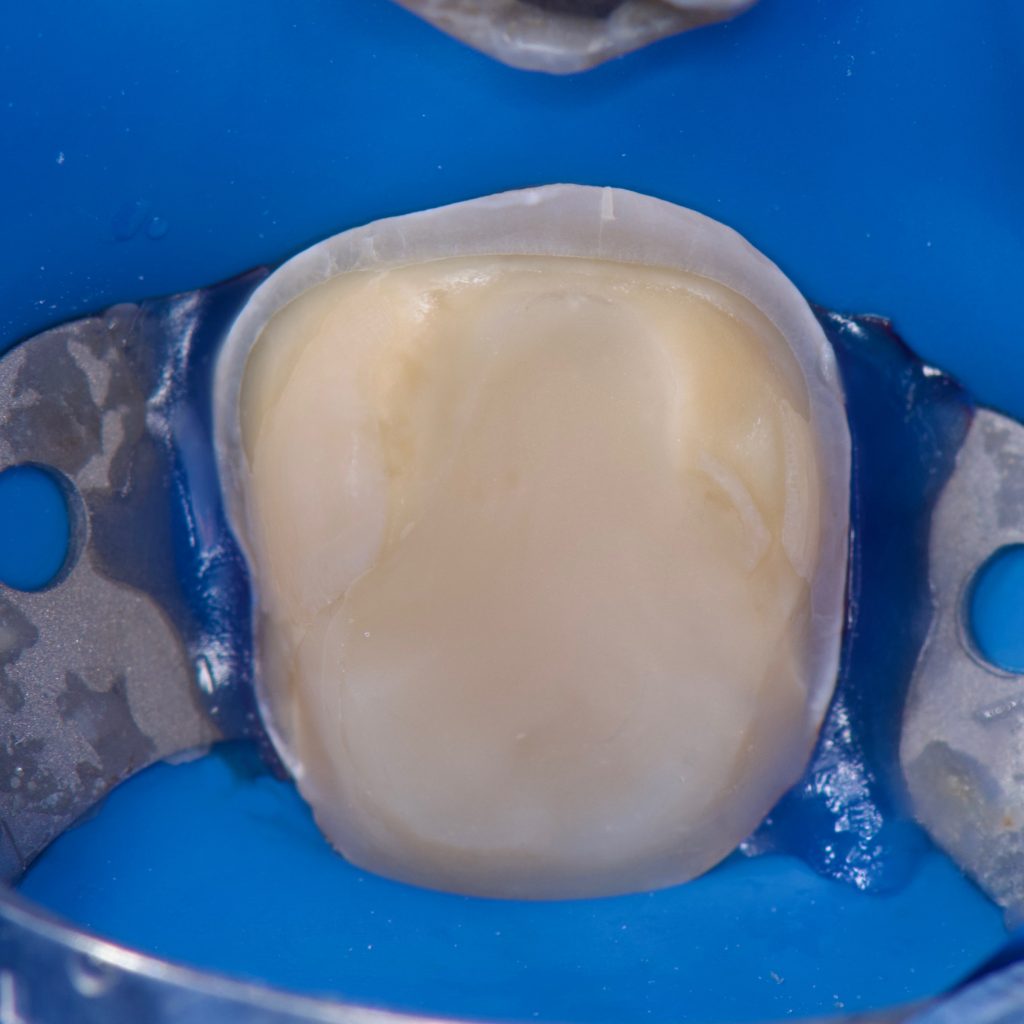

– E max crown bonded with Heated Ap-x composite